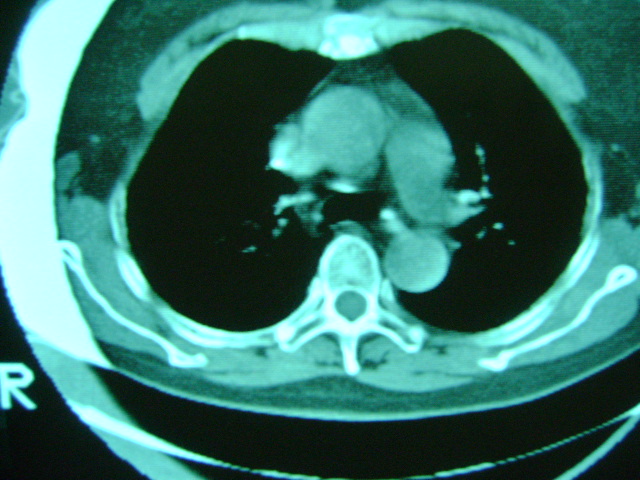

朋友的母亲,56y,咳嗽三个月,感觉左肺门不对,请大家给点意见

左肺门还可以吧

左肺门未见异常!

应该没问题,不放心就薄层扫描看看.

左肺门未见异常‘右肺有少许感染,图象质量不好